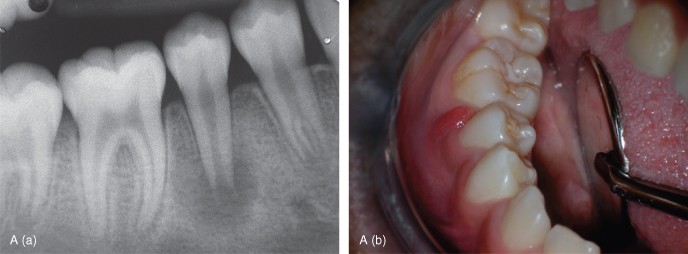

7. (Select ONE OR MORE correct answers)

The 13-year-old healthy boy presents with discomfort from lower right. What is/are the most likely diagnosis/es for tooth 4.5?